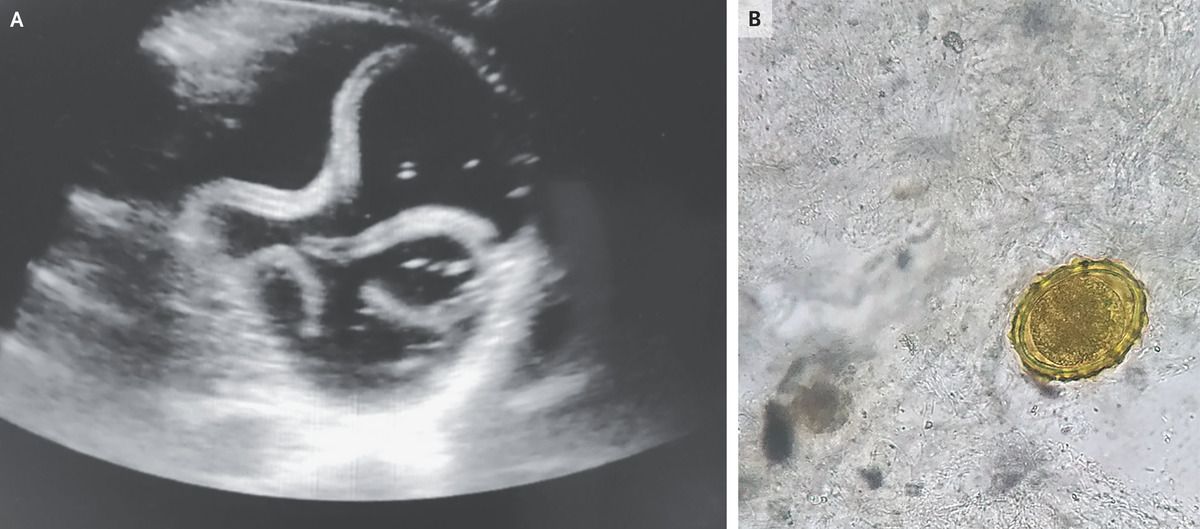

A 20-year-old man presented to the emergency department with a 1-day history of abdominal pain, diarrhea, and vomiting. He had previously been healthy, with no relevant medical history. The heart rate was 96 beats per minute, and the blood pressure was 96/60 mm Hg. On examination, the abdomen was soft and nontender. Laboratory studies showed a hemoglobin level of 19.5 g per deciliter (reference range, 12 to 15), a white-cell count of 20,800 per cubic millimeter (reference range, 4000 to 11,000) with 72.7% neutrophils, and an eosinophil count of 25 per cubic millimeter (reference range, 20 to 500). A point-of-care ultrasound examination of the inferior vena cava was performed to assess the patient’s intravascular fluid status. During the examination, a tubular echogenic structure that moved with a curling motion was seen inside the lumen of the stomach (Panel A and video). Examination of stool for ova and parasites revealed fertilized eggs from roundworms of the species Ascaris lumbricoides (Panel B), and a diagnosis of ascariasis was made. In addition to receiving intravenous fluids, the patient was given a single 400-mg dose of oral albendazole, and he was discharged after 1 day in the hospital. At follow-up in the outpatient clinic 2 weeks after discharge, he reported feeling well and noted that he had passed worms in his stool.